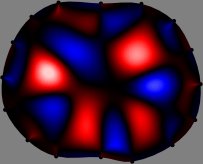

Figs. 3 and 4 compare the performance of the proposed FER method in (20) with the standard regularized least-squares method ((19) when \mathcal{R} is the identity matrix). The regularization parameter of the standard method was heuristically chosen for its best performance, and the parameter of the FER method was set to be one of three different values λ=0.05,0.2,𝜆0.050.2\lambda=0.05,0.2,\infty. The injection current was 1 mARMSRMS{}_{\tiny{\mbox{RMS}}} at 100 kHz, and the frame rate was 9 frames per second. The reference frame at t0subscript𝑡0t_{0} was obtained from the maximum expiration state. The measured data, 𝐕˙(tm)˙𝐕subscript𝑡𝑚\dot{\mathbf{V}}(t_{m}), represent the voltage differences between each time tmsubscript𝑡𝑚t_{m} and t0subscript𝑡0t_{0}. The blue regions, which denote where conductivity decreased by inhaled air, increased during inspiration and decreased during expiration. The FER method with λ=𝜆\lambda=\infty was clearly more robust than the standard method that produced more artifacts originated from the inversion process.

Figure 3: The reconstructed images of the conductivity change of the subject A by the standard regularized least square method and the proposed fidelity-embedded regularization (FER) method for three difference values λ=0.05,0.2,𝜆0.050.2\lambda=0.05,0.2,\infty. Here, the time step is 0.22 seconds (tm+2tm0.22subscript𝑡𝑚2subscript𝑡𝑚0.22t_{m+2}-t_{m}\approx 0.22).

Figure 4: The reconstructed images of the conductivity change of the subject B by the standard regularized least square method and the proposed fidelity-embedded regularization (FER) method for three difference values λ=0.05,0.2,𝜆0.050.2\lambda=0.05,0.2,\infty. Here, the time step is 0.55 seconds (tm+5tm0.55subscript𝑡𝑚5subscript𝑡𝑚0.55t_{m+5}-t_{m}\approx 0.55).